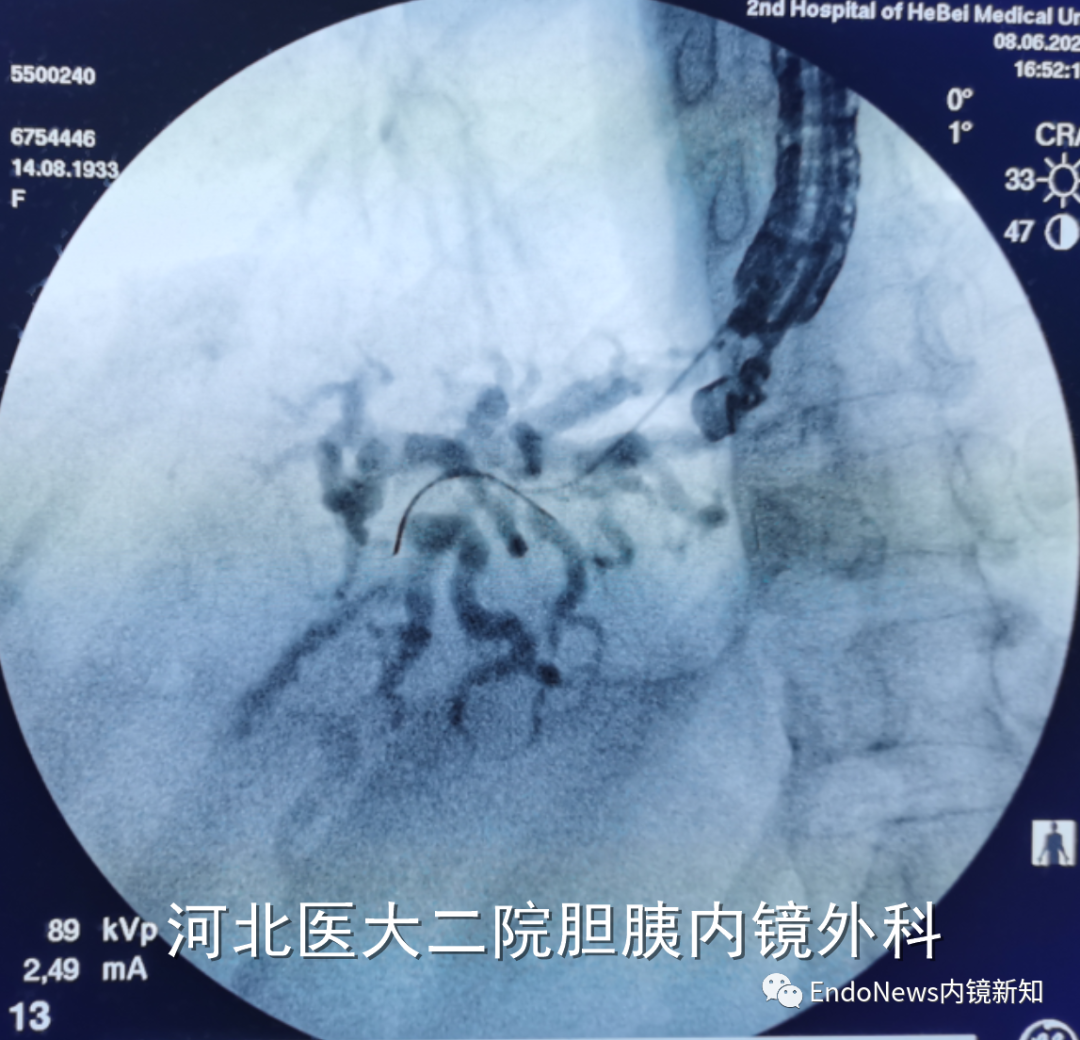

也有一些时候穿刺后导丝方向本身就是朝向胆总管下游方向的,比如下面两个病例:

幸运的是,此患者第一针穿刺即成功,随后注射造影剂(EACP),显影后可观察到如图1(a)中所示,这个患者肝内胆管分支很多,但是由于每支均比较细,不容易找到理想的目标穿刺胆管。

下一步进入导丝之后,我们发现导丝朝向胆管上游(即肝缘方向,如图1(b)中所示),这时需要用到此前提到的调整方法:将穿刺针和导丝往回撤,尤其穿刺针,要撤入到肝实质内,但要注意导丝不能往回撤太多,这个过程一定要在X线下谨慎操作。